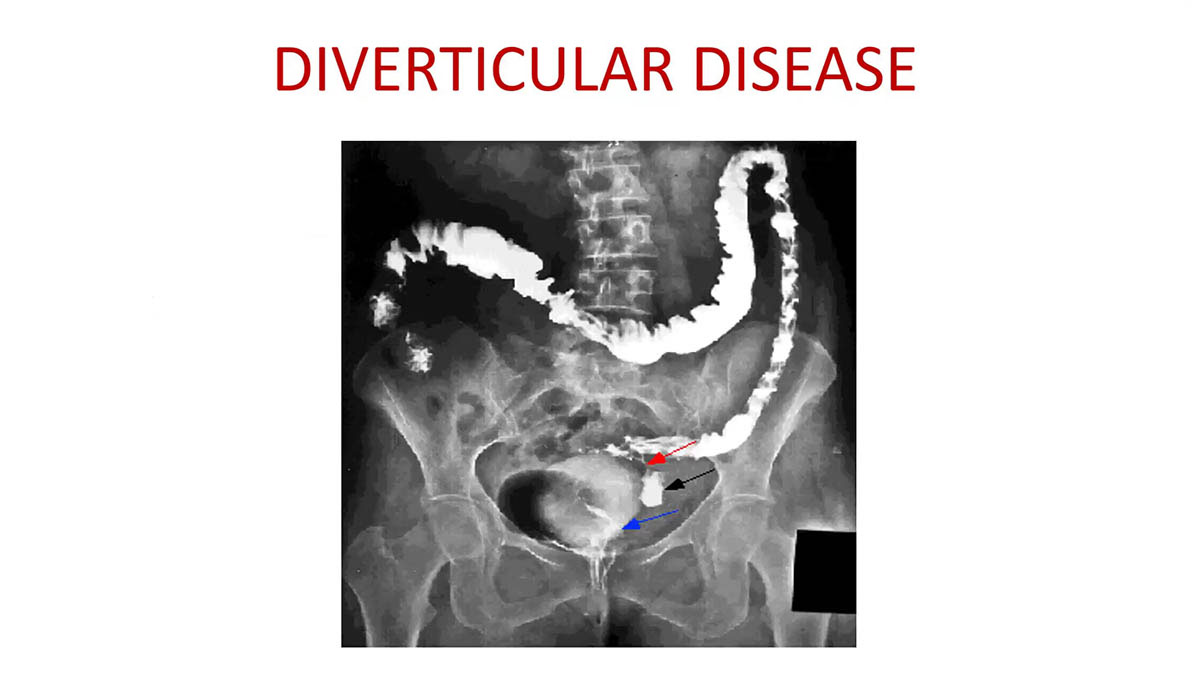

Diverticulosis X Ray

Learning Radiology - diverticulitis, diverticulosis Diverticular disease | Radiology Reference Article | Radiopaedia.org Barium X-ray showing colonic diverticula - Stock Image - M140/0083 - Science Photo Library Diverticulosis | Diverticulosis X Ray